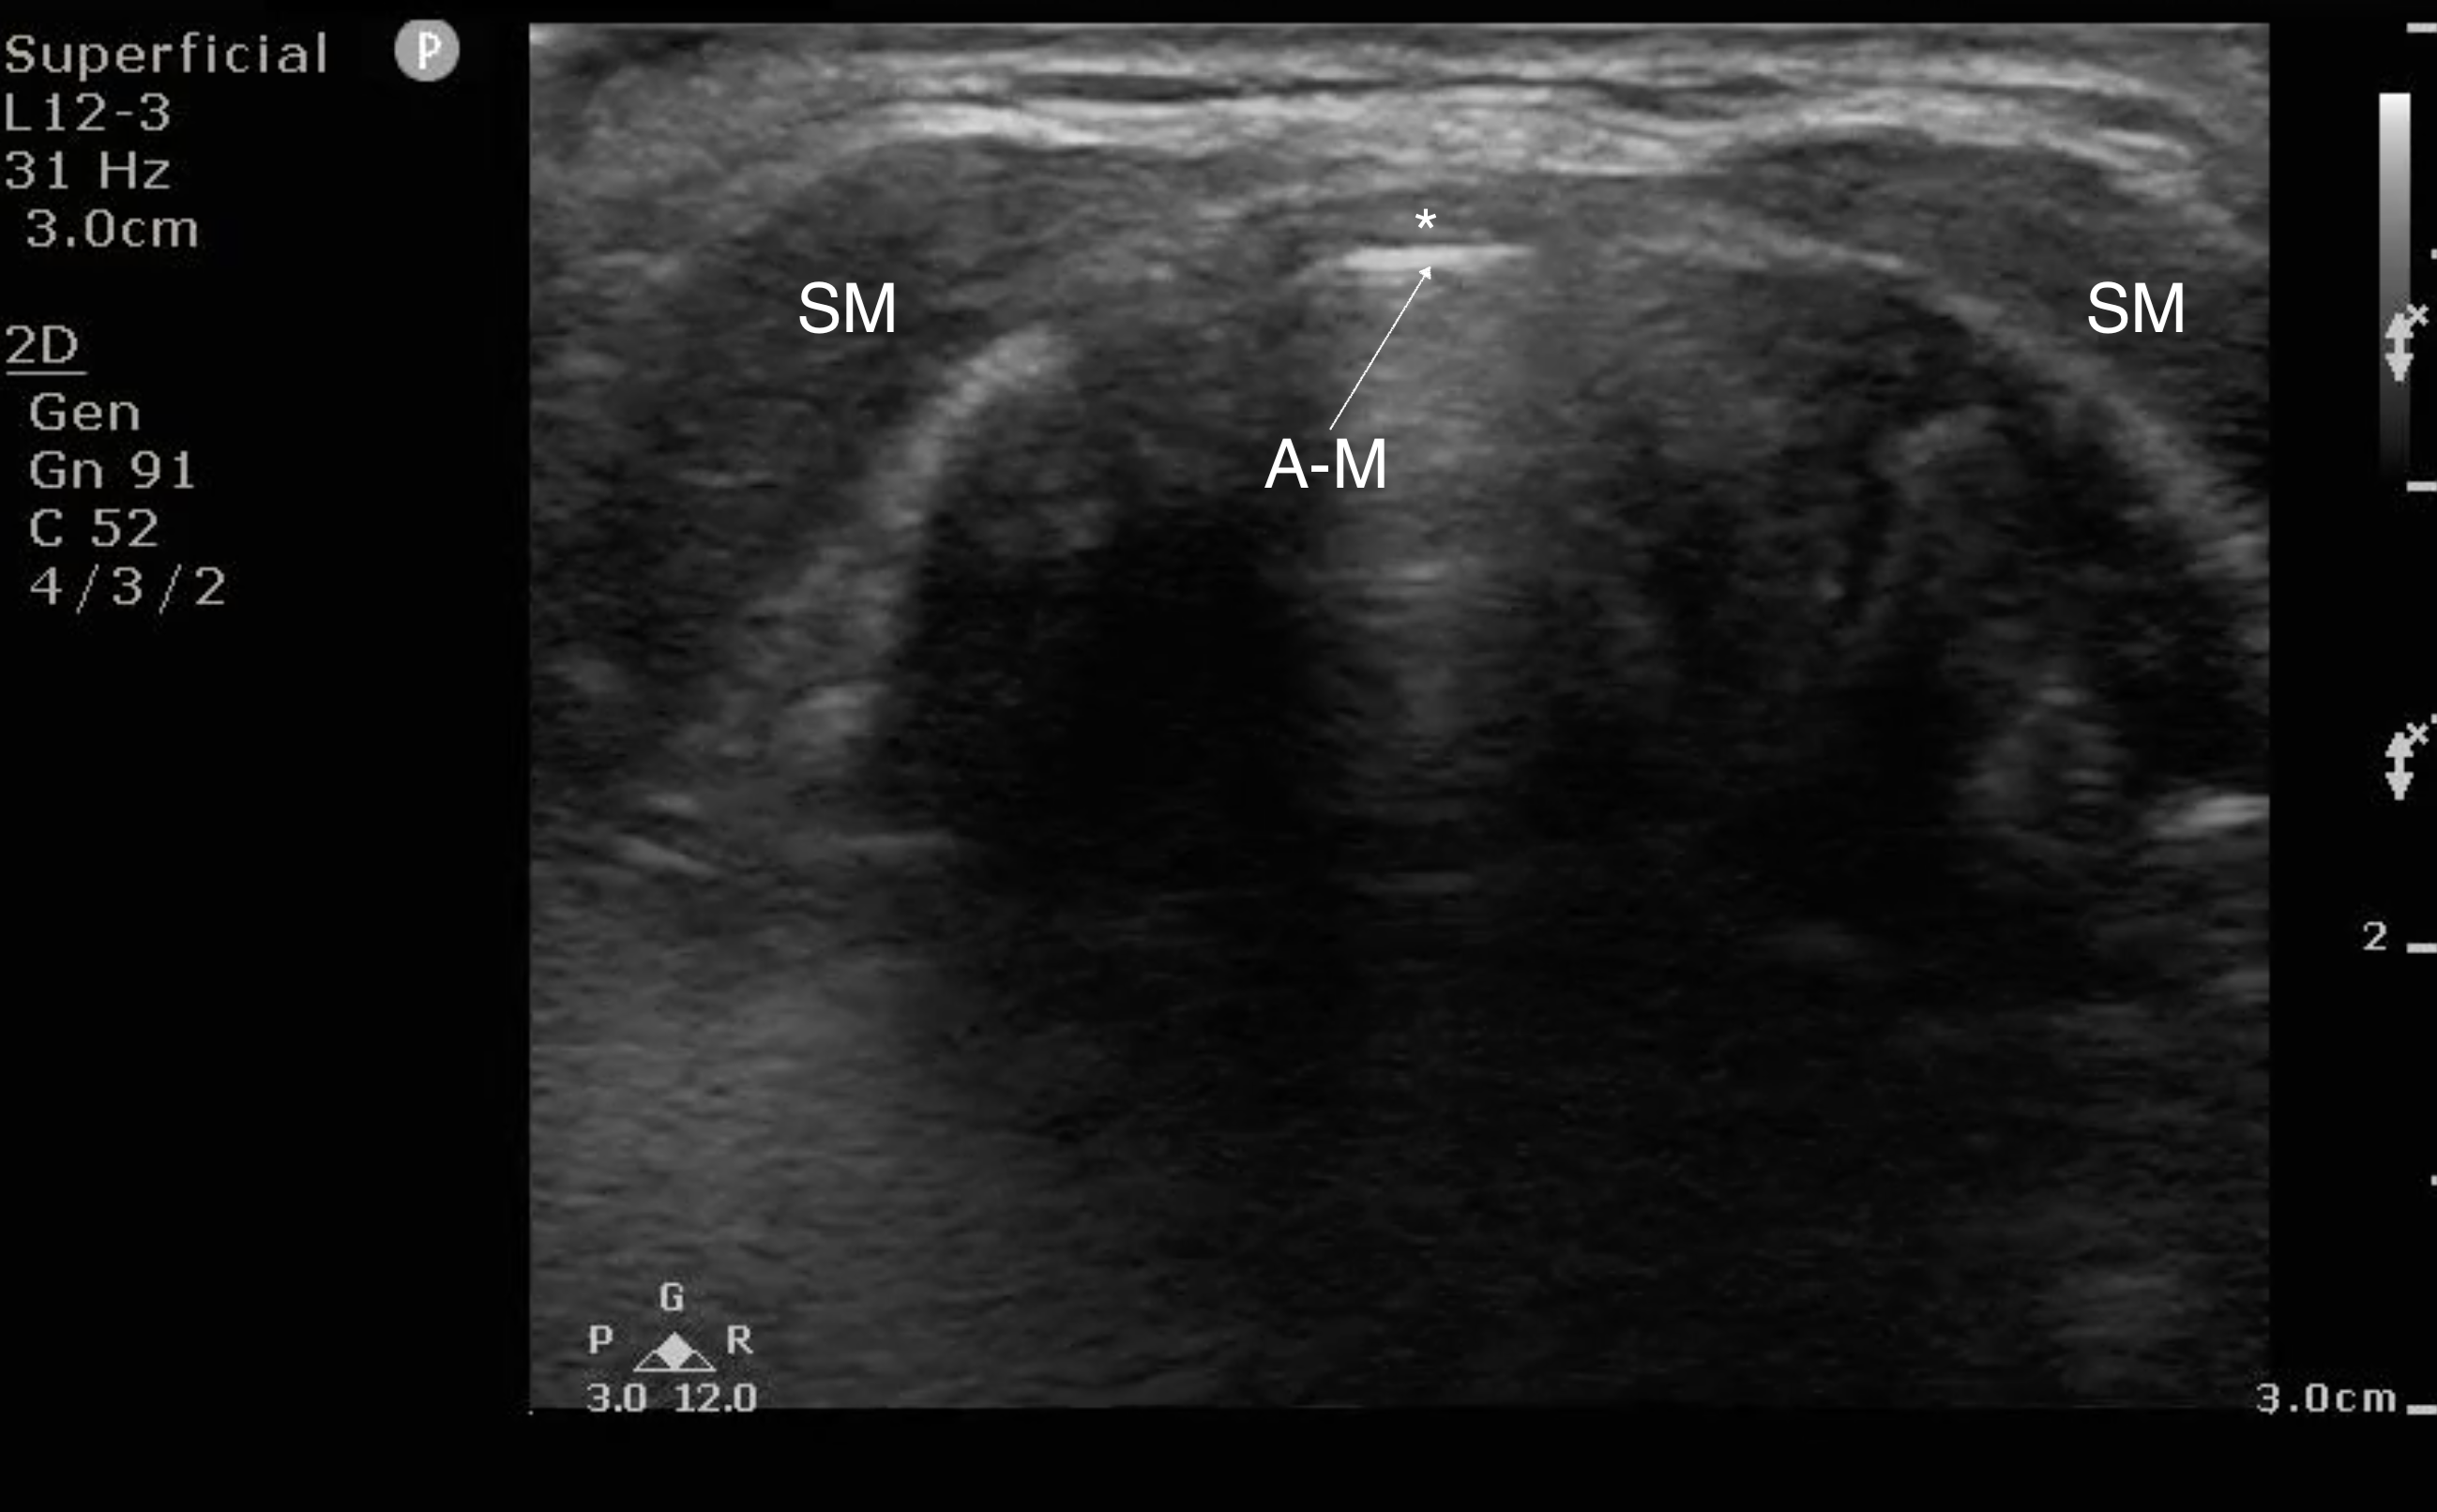

- Figure 5a and b. Step 5: Immediately below the thyroid cartilage is the cricothyroid membrane (*). Note there is no cartilage overlying the membrane, and directly deep to the membrane is the hyperechoic air-mucosal (A-M) interface.